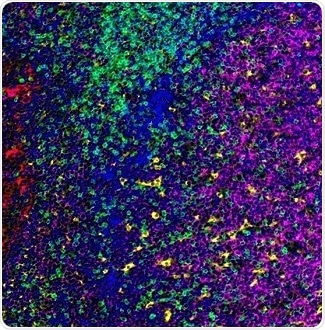

Figure 3. Detection of human CD3 (green), CD20 (magenta), CD68 (yellow), and cytokeratin (red) in FFPE tonsil by IHC-IF. Antibodies: Rabbit anti-CD3E recombinant monoclonal [BL-298-5D12] (A700-016), mouse anti-CD20 monoclonal [L26] (A500-017A), mouse anti-CD68 monoclonal [KP-1] (A500-018A), and mouse anti-Cytokeratin [AE1/AE3] (A500-019A). Secondary: HRP-conjugated goat anti-rabbit IgG (A120-501P) and HRP-conjugated goat anti-mouse IgG (A90-116P). Substrate: Opal™. Counterstain: DAPI (blue). Image Credit: Bethyl Laboratories Inc.